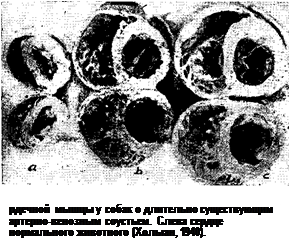

Гипертрофия миокарда у животных сартерио - венозной фистулой. Для того чтобы в результате образования артерио-венозной фистулы создалась значительная нагрузка на сердце, следует соблюдать ряд условий. Операция должна проводиться на крупных сосудах (аорта — нижняя полая вена; подвздошные, бедренные артерии и вены); длина соустья должна быть не менее 3—4 см: лучше накладывать две фистулы (между подвздошными или бедренными сосудами с обеих сторон). Холман (1940) изучил закономерности развития гипертрофии миокарда после образования сосудистого соустья (рис. 10). Последнее накладывалось у собак между аортой и нижней полой веной. Рентгенологическое исследование показало, что в течение первых 24—48 часов после наложения артерио-венозного соустья сердце уменьшается в размерах; в течение этого периода животное может погибнуть от шока. Если собака выживает, сердце достигает нормальных размеров, а затем начинает постепенно увеличиваться. Друри и Уайтман (1940) получали выраженную гипертрофию сердца у собак при наложении искусственного соустья между сонной артерией и наружной яремной веной.